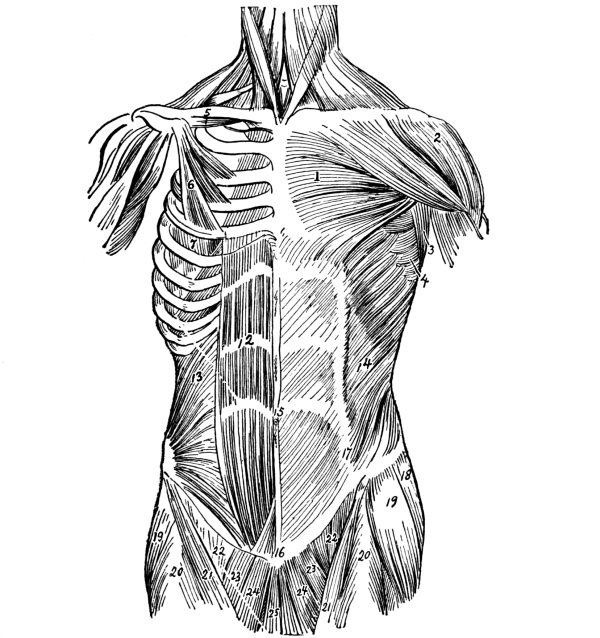

| The Chest | 96 |

The Sternum, 97—The Ribs, 97—Costal Cartilages, 98—Muscles of the Chest, 98—Diaphragm, 98—Mammary Glands, 100. |